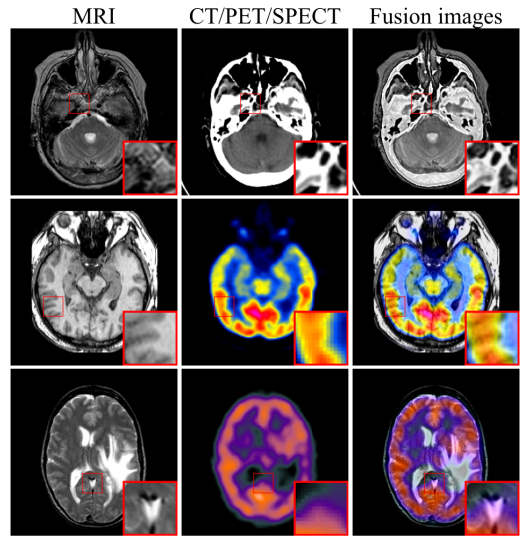

此外,为进一步有效地保留医学影像的纹理特征和强度信息,定义了包含内容损失和强度损失的联合损失函数来约束融合模块,并引入自适应权重来控制源图像的信息保留程度。所提出的框架在CT-MRI、PET-MRI和SPECT-MRI等多个融合任务上进行实验,通过定性和定量分析验证了模型的优越性。